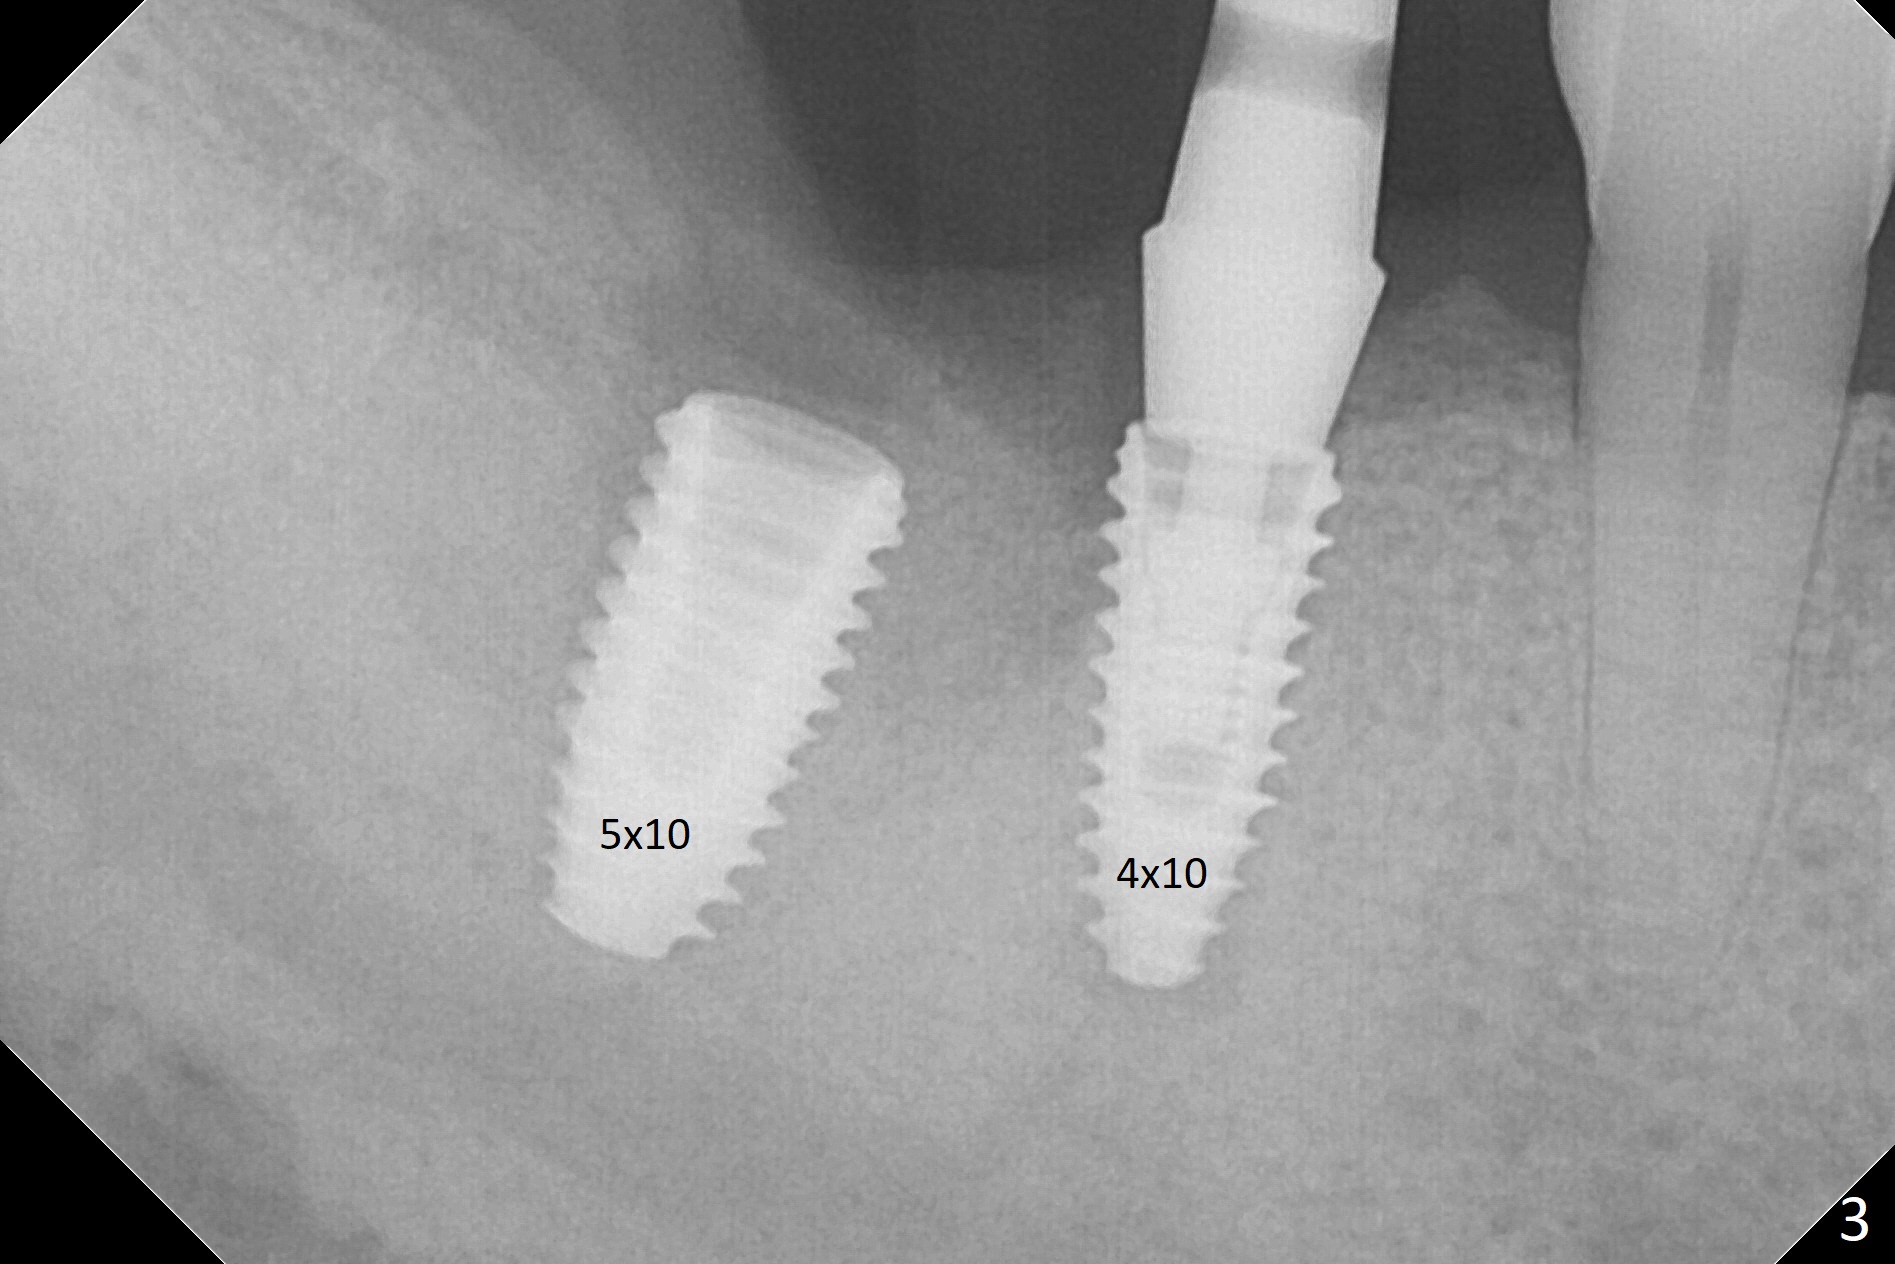

Osteotomy at the sites of #30 and 31 is initiated with Magic Split, followed by Magic Expanders (3.0 and 3.8 mm) at #31. Initial depth of osteotomy is 13 mm with 2.2 mm drill (Fig.1). After adjustment of the trajectory at #31 (Fig.1 arrow) and deepening the osteotomy by 2 mm, dummy implants are placed with stability (Fig.2). Following increase in osteotomy at #31, the larger implant in fact loses stability (Fig.3). The loose implant is pushed distal (Fig.4 arrow) with placement of autogenous bone mesial (*). The stable implant at #30 (Fig.3) and its abutment (Fig.4) are used as a post to hold periodontal dressing, which covers the wound at #31 after placement of collagen plug and suturing. In fact the same technique could be used when socket preservation was performed if an implant were placed at #30 at the same time. When the periodontal dressing dislodges, the wound at #31 heals uneventfully (Fig.5,6). The bone graft seems to remain in place 3 months postop (Fig.7). The implant is uncovered with placement of a 6.8x7 mm healing abutment 4 months postop. When a cementation abutment is placed and prepped, the buccal margin is much lower than the lingual (Fig.8 taken prior to cementation). The patient enjoys mastication with the new implant crowns 3.5 months post cementation (Fig.9).